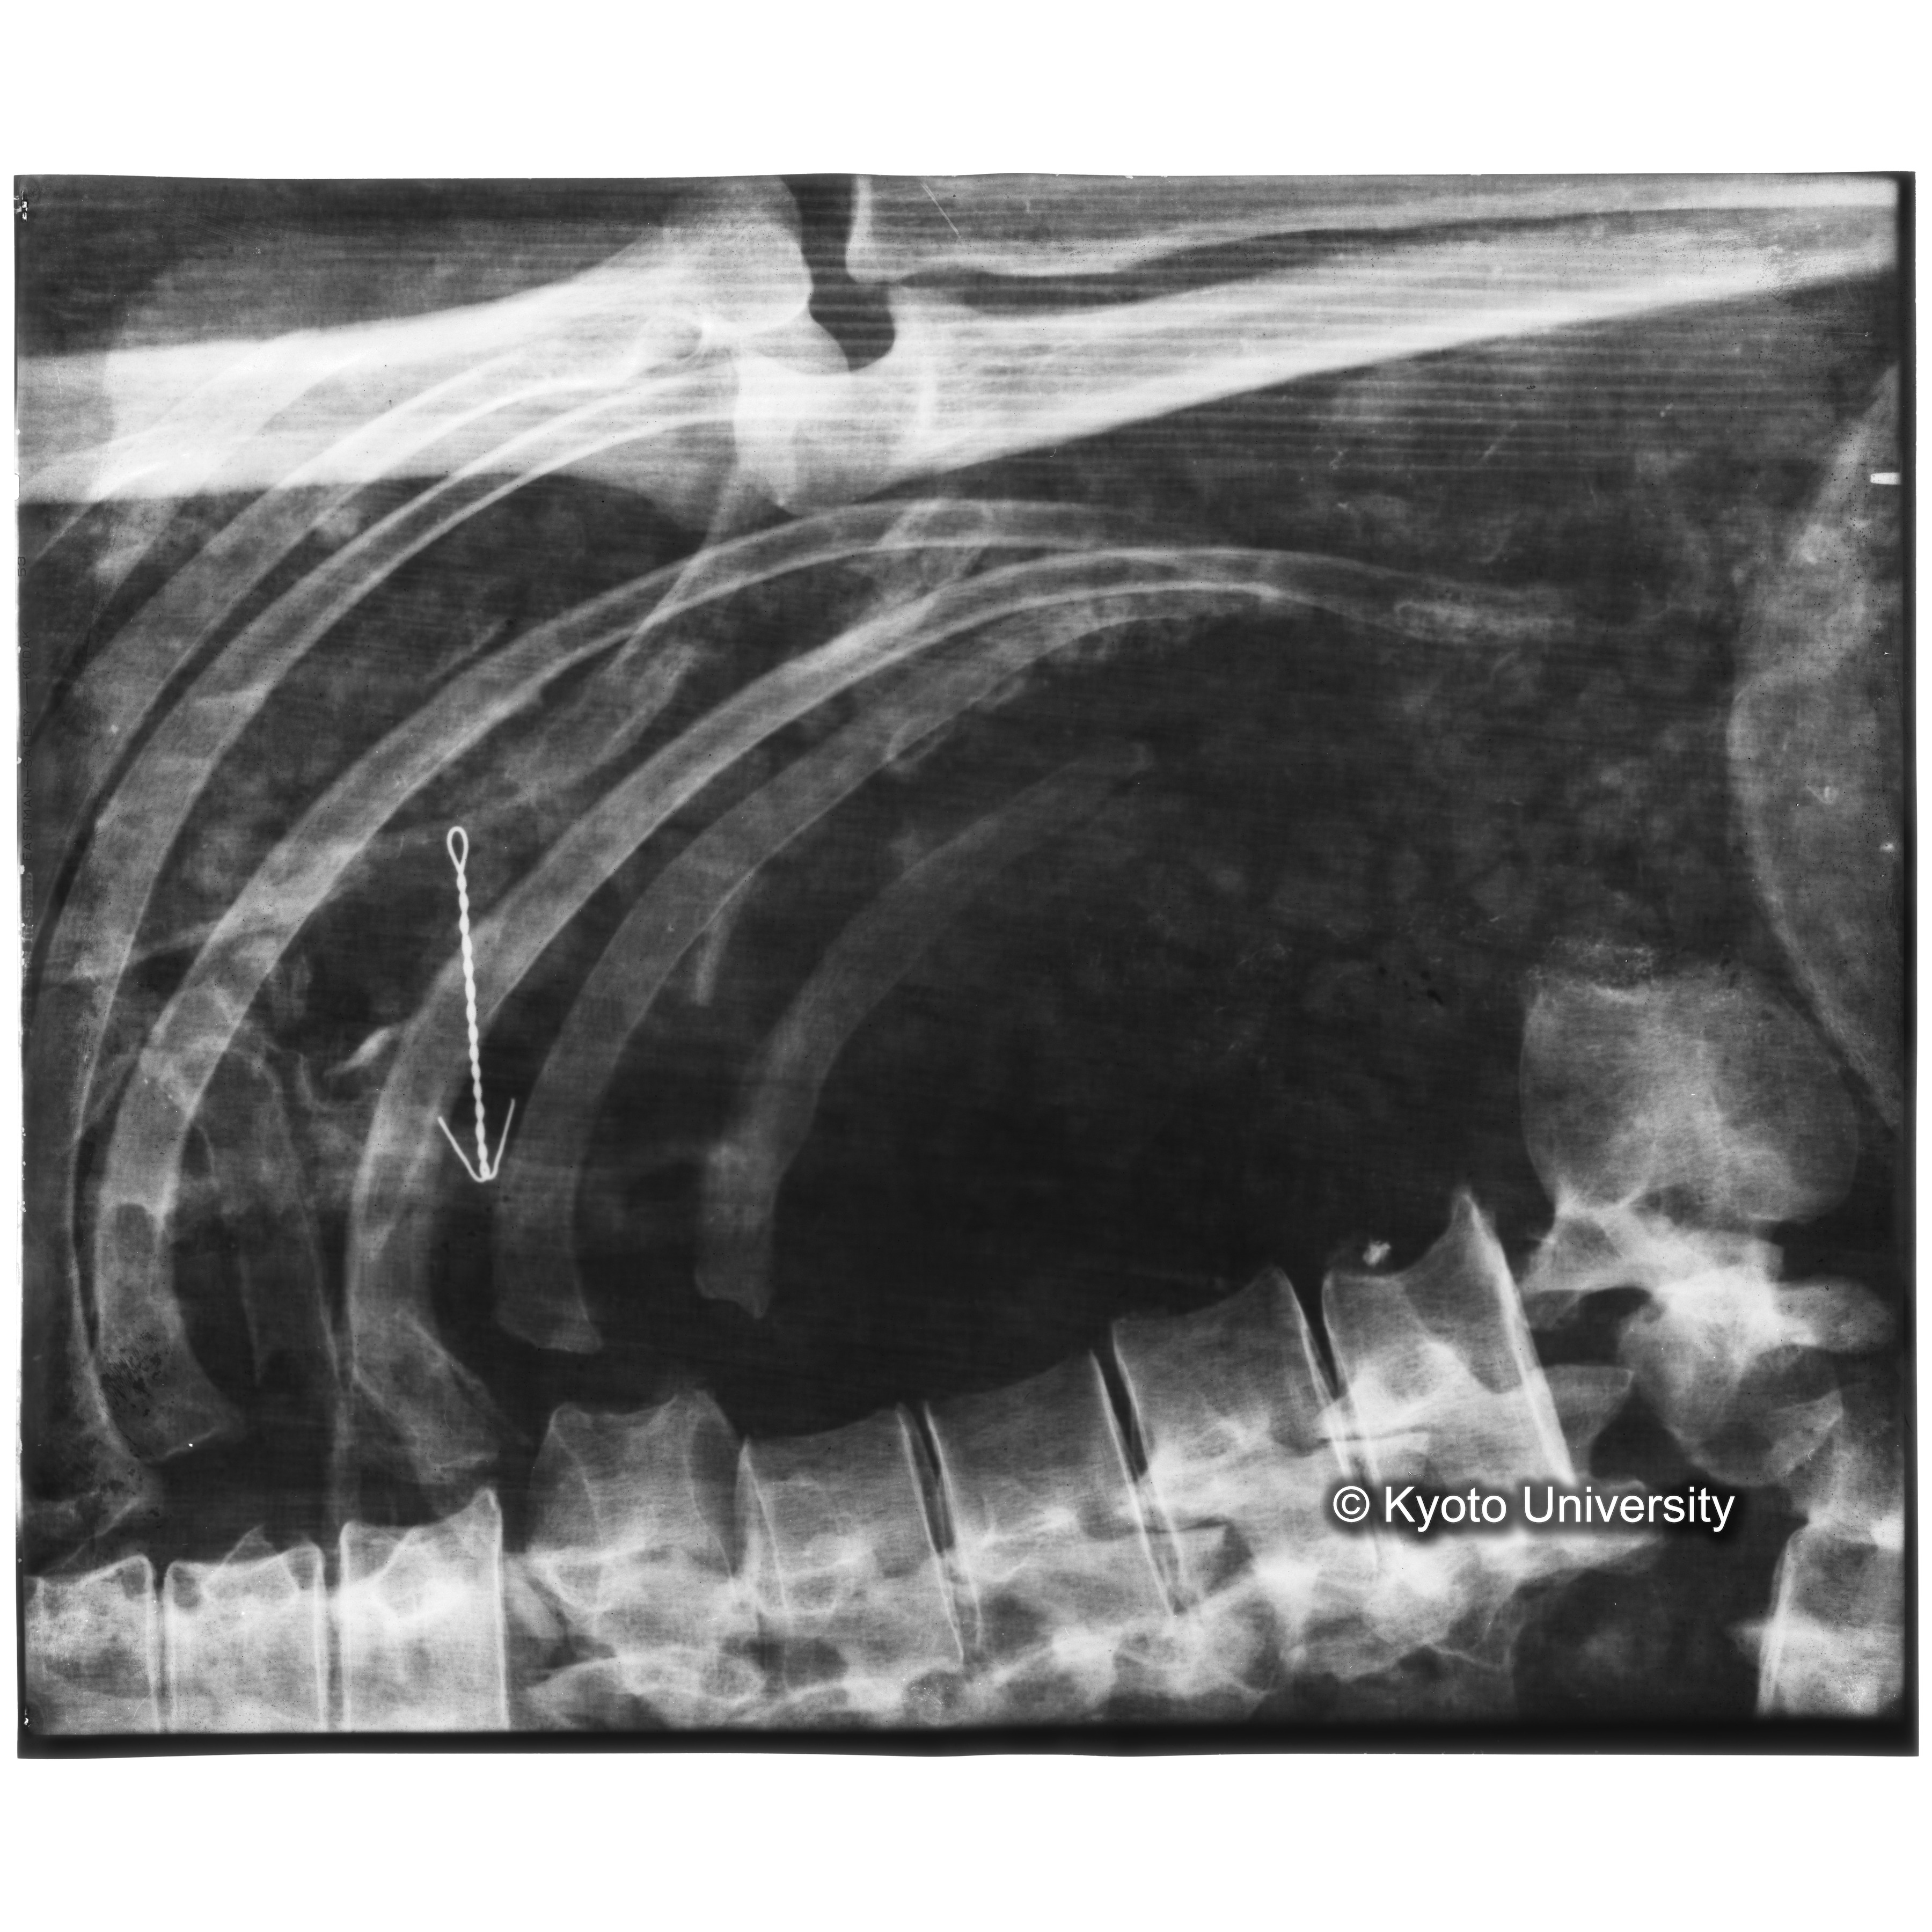

[写真内容] 胸部レントゲン

「蘇った古代の木乃伊-藤原鎌足-」における119頁の「44 胸部レントゲン」にコンテンツを右に90度回転したものが対応している.